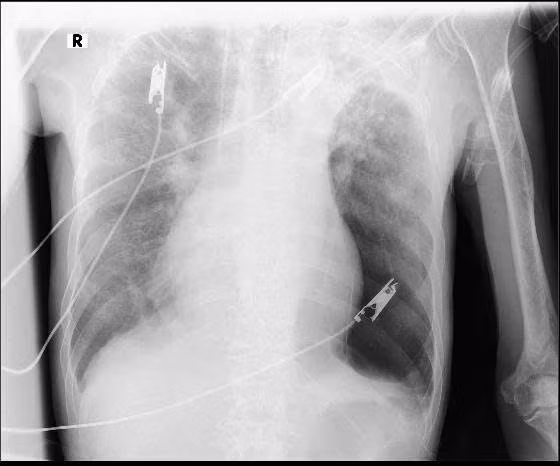

hut-thuoc4.jpg

Phổi của bệnh nhân trên phim chụp - Ảnh BVCC

Kết quả chẩn đoán hình ảnh cho thấy tổn thương phổi hai bên rất nặng, kèm theo tràn dịch màng phổi bên phải và tràn khí màng phổi bên trái. Xét nghiệm đờm phát hiện trực khuẩn kháng cồn – kháng toan, gợi ý lao phổi đang hoạt động trên nền phổi đã bị phá hủy kéo dài.

Theo ThS.BS Trương Tư Thế Bảo, đây là hậu quả điển hình của lao phổi không được điều trị triệt để, kết hợp với việc hút thuốc lá và lạm dụng rượu bia trong nhiều năm, khiến cấu trúc phổi bị tổn thương lan tỏa, khả năng trao đổi khí suy giảm nghiêm trọng và rất khó hồi phục.